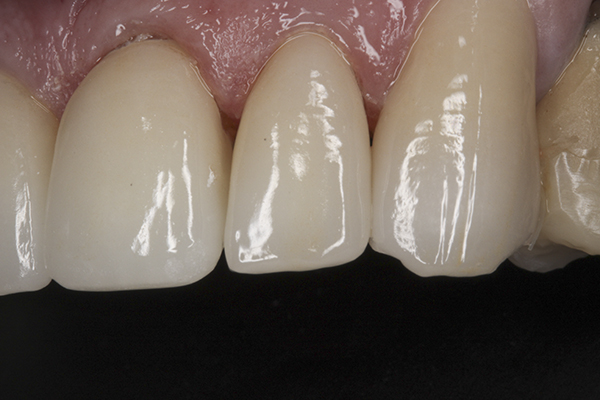

(13.) Preoperative anterior, close-up view.

Figure 13